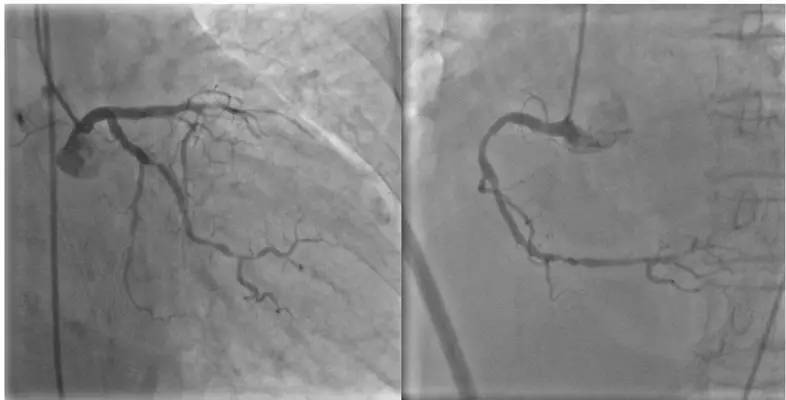

诊疗经过2:溶栓2小时后,患者胸痛无明显缓解,心电图ST段亦无明显回落。于15小时后转入上级医院CCU,患者仍持续喘憋,咳嗽、咳白色泡沫痰,不能平卧。查体:BP 150/75 mmHg,P 110次/分,R 30次/分,口唇发绀,双下肺可闻及细湿啰音,考虑患者急性心肌梗死合并急性左心衰。立即予呋塞米20 mg静推,硝酸甘油10μg/min静点,阿司匹林、氯吡格雷各300 mg抗血小板治疗。10分钟后患者症状有所好转,遂决定在主动脉内球囊反搏(IABP)辅助下行PCI治疗。30分钟后进入导管室,首先将IABP置入降主动脉起始端,以1:1反搏频率辅助。冠脉造影提示LAD近段闭塞;LCX远段狭窄70%,OM开口狭窄90%;RCA弥漫性病变,近段狭窄60%,远段狭窄80%(图3)。判断LAD为罪犯血管,球囊扩张LAD中段,扩后残余狭窄30%,随后于LAD中段及近段依次置入2枚支架,复查造影提示狭窄解除,血流恢复TIMI3级。

图3